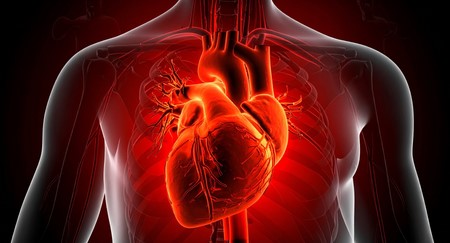

Zemra që përpiqet të shërohet, rigjenerimi i pjesshëm pas infarktit dhe kufijtë e shpresës biologjike

Për dekada me radhë, mjekësia ka mbajtur si dogmë idenë se zemra e njeriut është një organ pothuajse i paaftë për rigjenerim. Ndryshe nga lëkura apo mëlçia, qelizat e muskulit kardiak (kardiomiocitet) konsideroheshin të “ngrirë” biologjikisht, të lindura për të punuar gjithë jetën, por jo për t’u zëvendësuar. Megjithatë, një zbulim i rëndësishëm shkencor e ka vënë këtë bindje në pikëpyetje.

Studiues të udhëhequr nga Universiteti i Sidnejt kanë treguar se zemra e njeriut zotëron një aftësi të kufizuar, por reale, për rigjenerim pas një infarkti. Pas dëmtimit të shkaktuar nga ndërprerja e furnizimit me gjak, qelizat e muskulit të zemrës nisin të ndahen dhe të riprodhohen në një masë më të madhe sesa mendohej më parë. Ky proces, megjithatë, nuk është i mjaftueshëm për të parandaluar formimin e indit fibroz (indi mbresor), i cili zë vendin e qelizave të vdekura dhe ul ndjeshëm efikasitetin e pompimit kardiak.

Rezultatet treguan qartë se ndarja dhe përhapja e kardiomiociteve rritet pas një ataku në zemër, një fenomen që deri më tani ishte dokumentuar kryesisht tek modelet shtazore, veçanërisht tek minjtë. Zbulimi përmbys një hendek të rëndësishëm midis biologjisë eksperimentale dhe realitetit njerëzor, duke dëshmuar se zemra nuk është thjesht një mekanizëm i pandryshueshëm, por një organ me një potencial adaptiv të nënvlerësuar.

Në thelb, zemra përpiqet të shërohet, por nuk arrin të rikthejë plotësisht strukturën dhe funksionin e saj fillestar. Pikërisht këtu qëndron edhe rëndësia më e madhe e këtij studimi: jo si zgjidhje përfundimtare, por si një portë e re drejt terapive rigjeneruese. Kuptimi i mekanizmave natyrorë të riprodhimit qelizor hap rrugën për ndërhyrje të synuara, që në të ardhmen mund të përforcojnë këtë aftësi të brendshme të zemrës.

Në një botë ku sëmundjet kardiovaskulare mbeten shkaku kryesor i vdekjes në nivel global, ky zbulim përfaqëson më shumë sesa një arritje laboratorike. Ai është një ndryshim paradigme: një ftesë për të rimenduar kufijtë biologjikë të njeriut dhe për të besuar se edhe organi që simbolizon jetën dhe emocionin – zemra – nuk është plotësisht i dorëzuar përballë dëmtimit, por ruan brenda vetes një potencial modest, por premtues, për t’u rilindur.